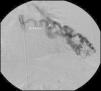

Para confirmar que a malformação vascular detetada era exclusivamente de natureza arterial foi efetuada angiografia seletiva da 4a à 7a artérias intercostais esquerdas que, além de revelar aumento do calibre das artérias intercostais (figs. 9 e 10), demonstrou fístula exclusivamente arterial entre os ramos da circulação sistémica acima referidos e o ramo esquerdo da artéria pulmonar através de novelo arterial (figs. 10 e 11). As artérias brônquicas, nomeadamente as do mesmo lado da malformação descrita, não foram avaliadas angiograficamente.